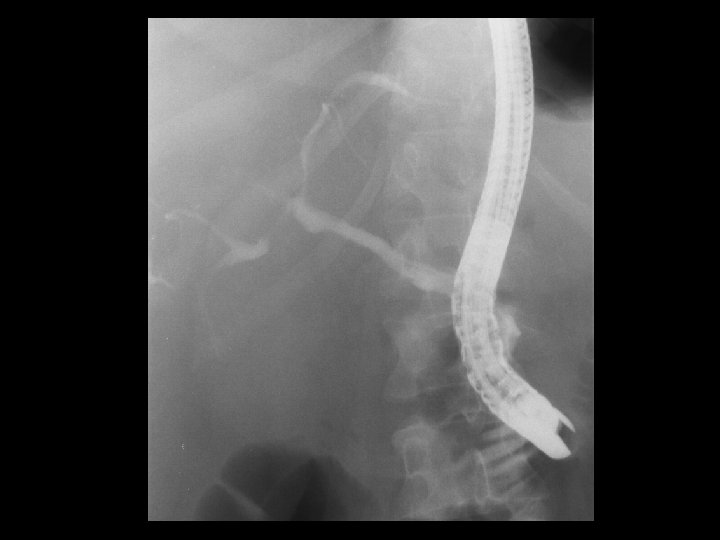

Cholangiocarcinoma • Findings: – ERCP shows diffuse irregular narrowing of the CBD and intrahepatic biliary tree • ddx: – Scerlosing cholangitis – Ascending cholangitis – AIDS cholangiopathy